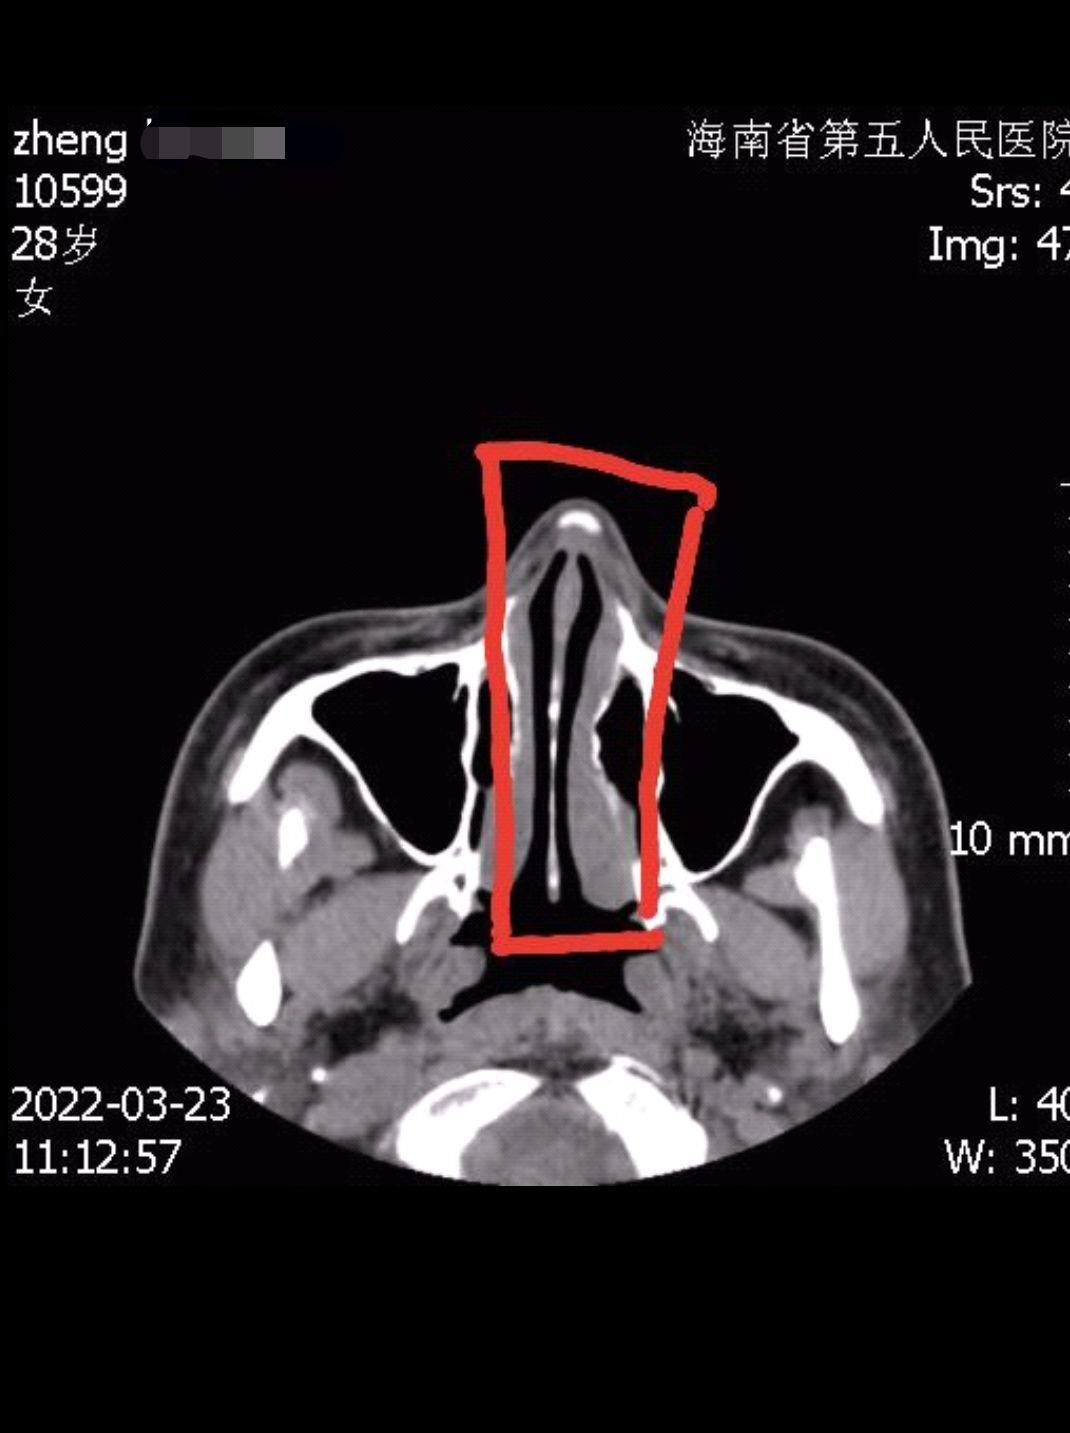

郑女士在整完后,身边人提醒她,鼻子怎么变歪了,她对着镜子细细端详,感觉鼻子确实被整歪了,为了证实不是眼神和角度问题,她便去海南省第五人民医院拍片。“人的主观视觉可能会看走眼,但机器固定拍摄,骗不了人,片子拍出来后,海南省第五人民医院的医生明确告诉我,鼻子里面放的假体没有放正,歪了3毫米左右,所以鼻子是歪的。”郑女士指着鼻子的X光片说,这肉眼可见假体是歪斜的,无论是从侧面、正面,还是上面,任何角度都是歪的。“我现在是欲哭无泪,只想赶快凑够钱,把假体取出来,再也不因为别人制造的面容焦虑而去整形了。”郑女士懊恼地说道。

当天,记者实地走访海南优姿妍医疗美容门诊部,现场有数名医美消费者在准备整形,为了不影响该医疗美容门诊部日常运行,记者便在一间办公室进行采访。起初,海南优姿妍医疗美容门诊部一名主管接受采访,对方告诉记者,机构负责人因身体问题,不方便出面接受采访,随后查看了郑女士提供的X光片子,表示没看出假体歪斜。在郑女士指出歪斜处后,该主管这才承认了歪斜事实。